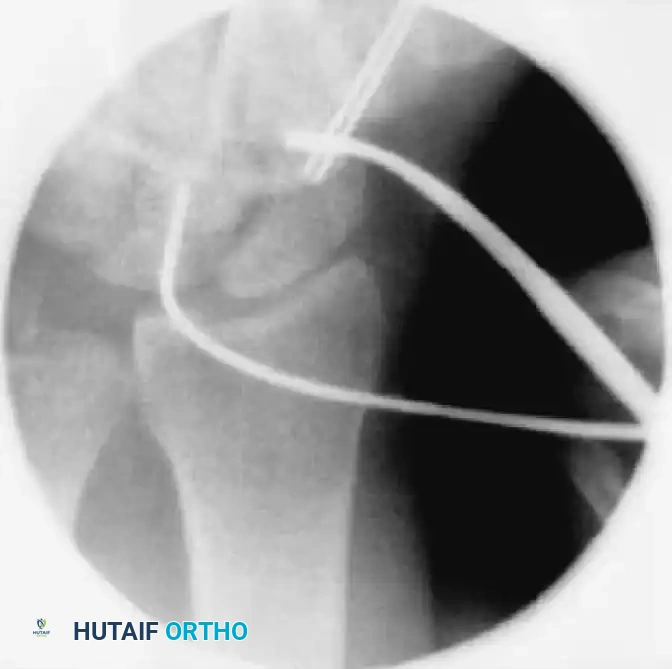

1. Fluoroscopic Targeting and The "Ring Sign"

The cornerstone of the Slade percutaneous dorsal approach is achieving the correct fluoroscopic view to target the central axis of the scaphoid.

• Achieving the Ring Sign: Gently pronate and flex the patient's wrist. Because the scaphoid sits obliquely, flexing and pronating the wrist aligns the proximal and distal poles coaxially with the fluoroscopy beam.

• When perfectly aligned, the scaphoid will project a cortical "ring" appearance on the fluoroscopic monitor. The exact center of this "ring" represents the central axis of the scaphoid—the optimal starting point for the guidewire.

FIGURE: Percutaneous fixation of scaphoid fracture. (A) Central axis of scaphoid located on PA view. (B) Wrist pronated until poles align. (C) Wrist flexed until the scaphoid demonstrates the classic "ring" appearance, indicating coaxial alignment.